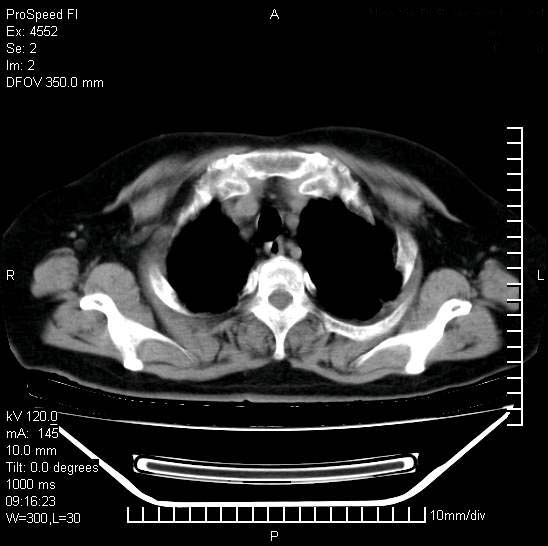

十几年前曾患肺结核,一周前突咳血约100ml,中性粒细胞稍高,诊断两上肺陈旧结核,下肺炎症,给予抗炎治疗,近几日晚上高热,39度,仍咳少量血,4天前ct及今天ct上传。

今天ct